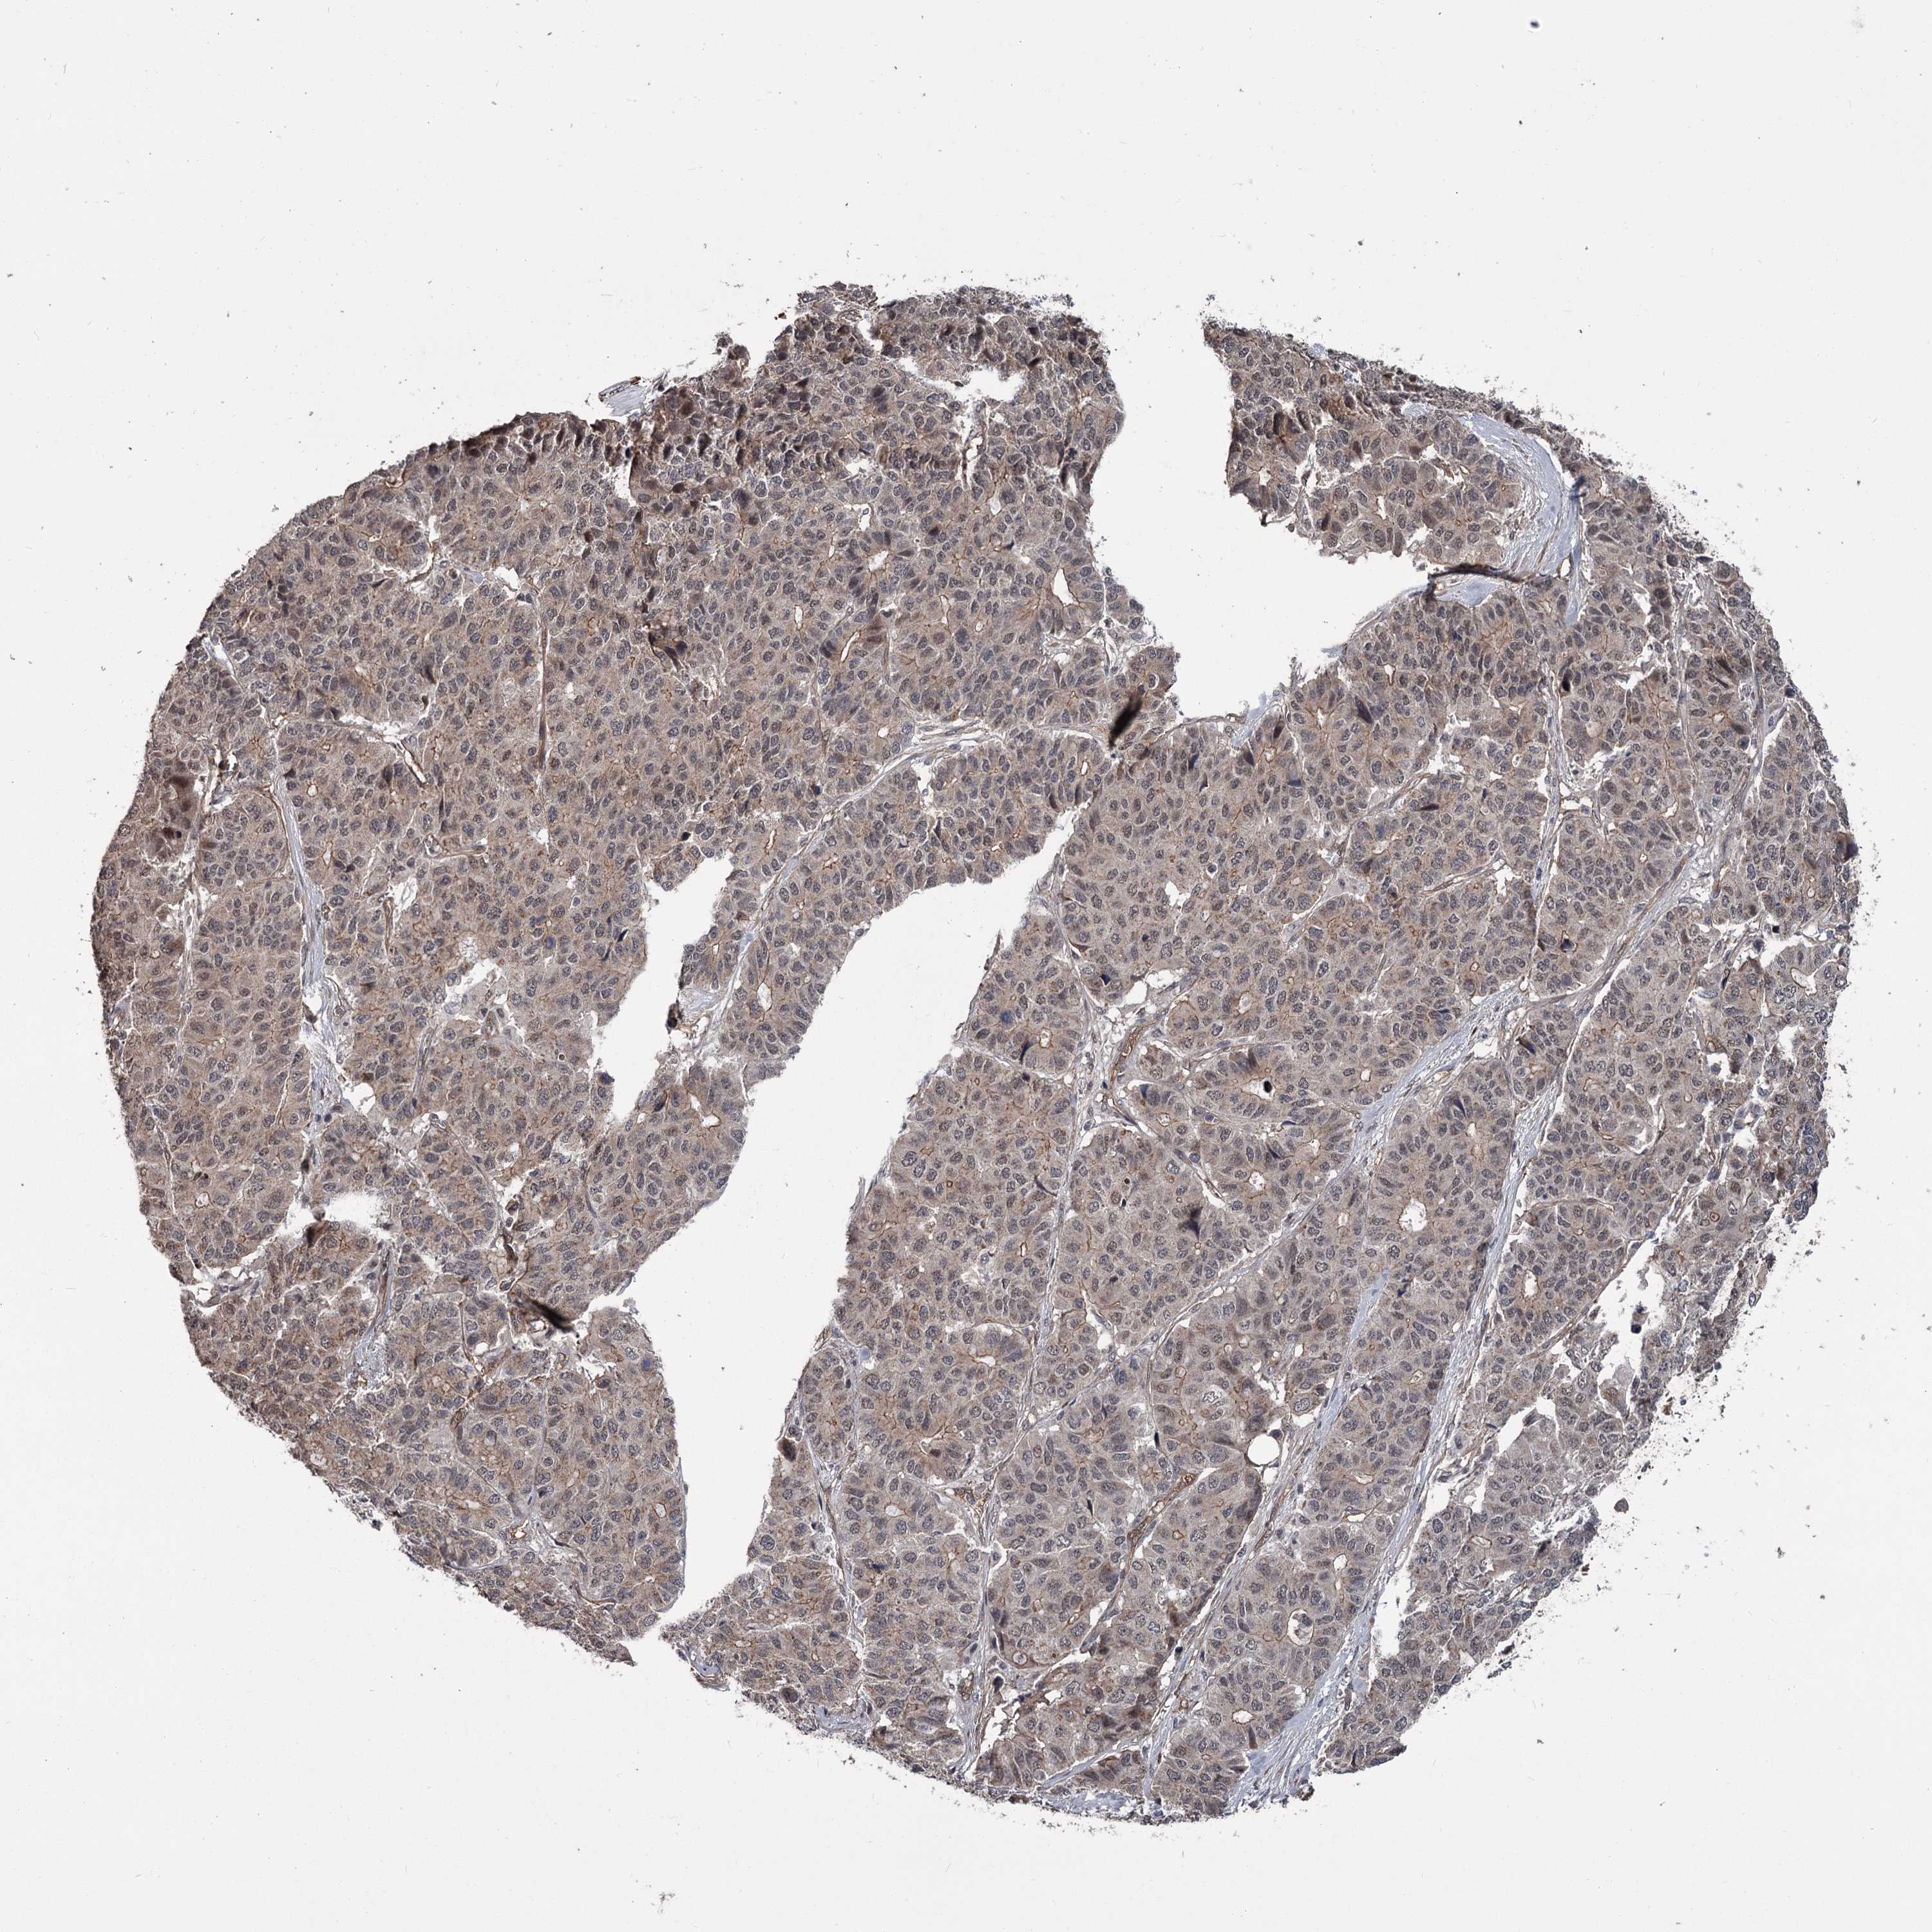

PANCREATIC CANCER - Protein expressioni

A mouse-over function shows sample information and annotation data. Click on an image to view it in a full screen mode. Samples can be filtered based on level of antibody staining by selecting one or several of the following categories: high, medium, low and not detected. The assay and annotation is described here.

Note that samples used for immunohistochemistry by the Human Protein Atlas do not correspond to samples in the TCGA dataset.

Antibody stainingi

Antibody staining in the annotated cell types in the current human tissue is reported as not detected, low, medium, or high, based on conventional immunohistochemistry profiling in selected tissues. This score is based on the combination of the staining intensity and fraction of stained cells.

Each image is clickable and will lead to virtual microscopy that enables deeper exploration of all samples and also displays staining intensity scores, fraction scores and subcellular localization as well as patient and tissue information for each sample.

Antibody HPA038562

Staining

High

Medium

Low

Not detected

Intensity

Strong

Moderate

Weak

Negative

Quantity

>75%

75%-25%

<25%

None

Location

Nuclear

Cytoplasmic/membranous

Cytoplasmic/membranous,nuclear

Adenocarcinoma, NOS